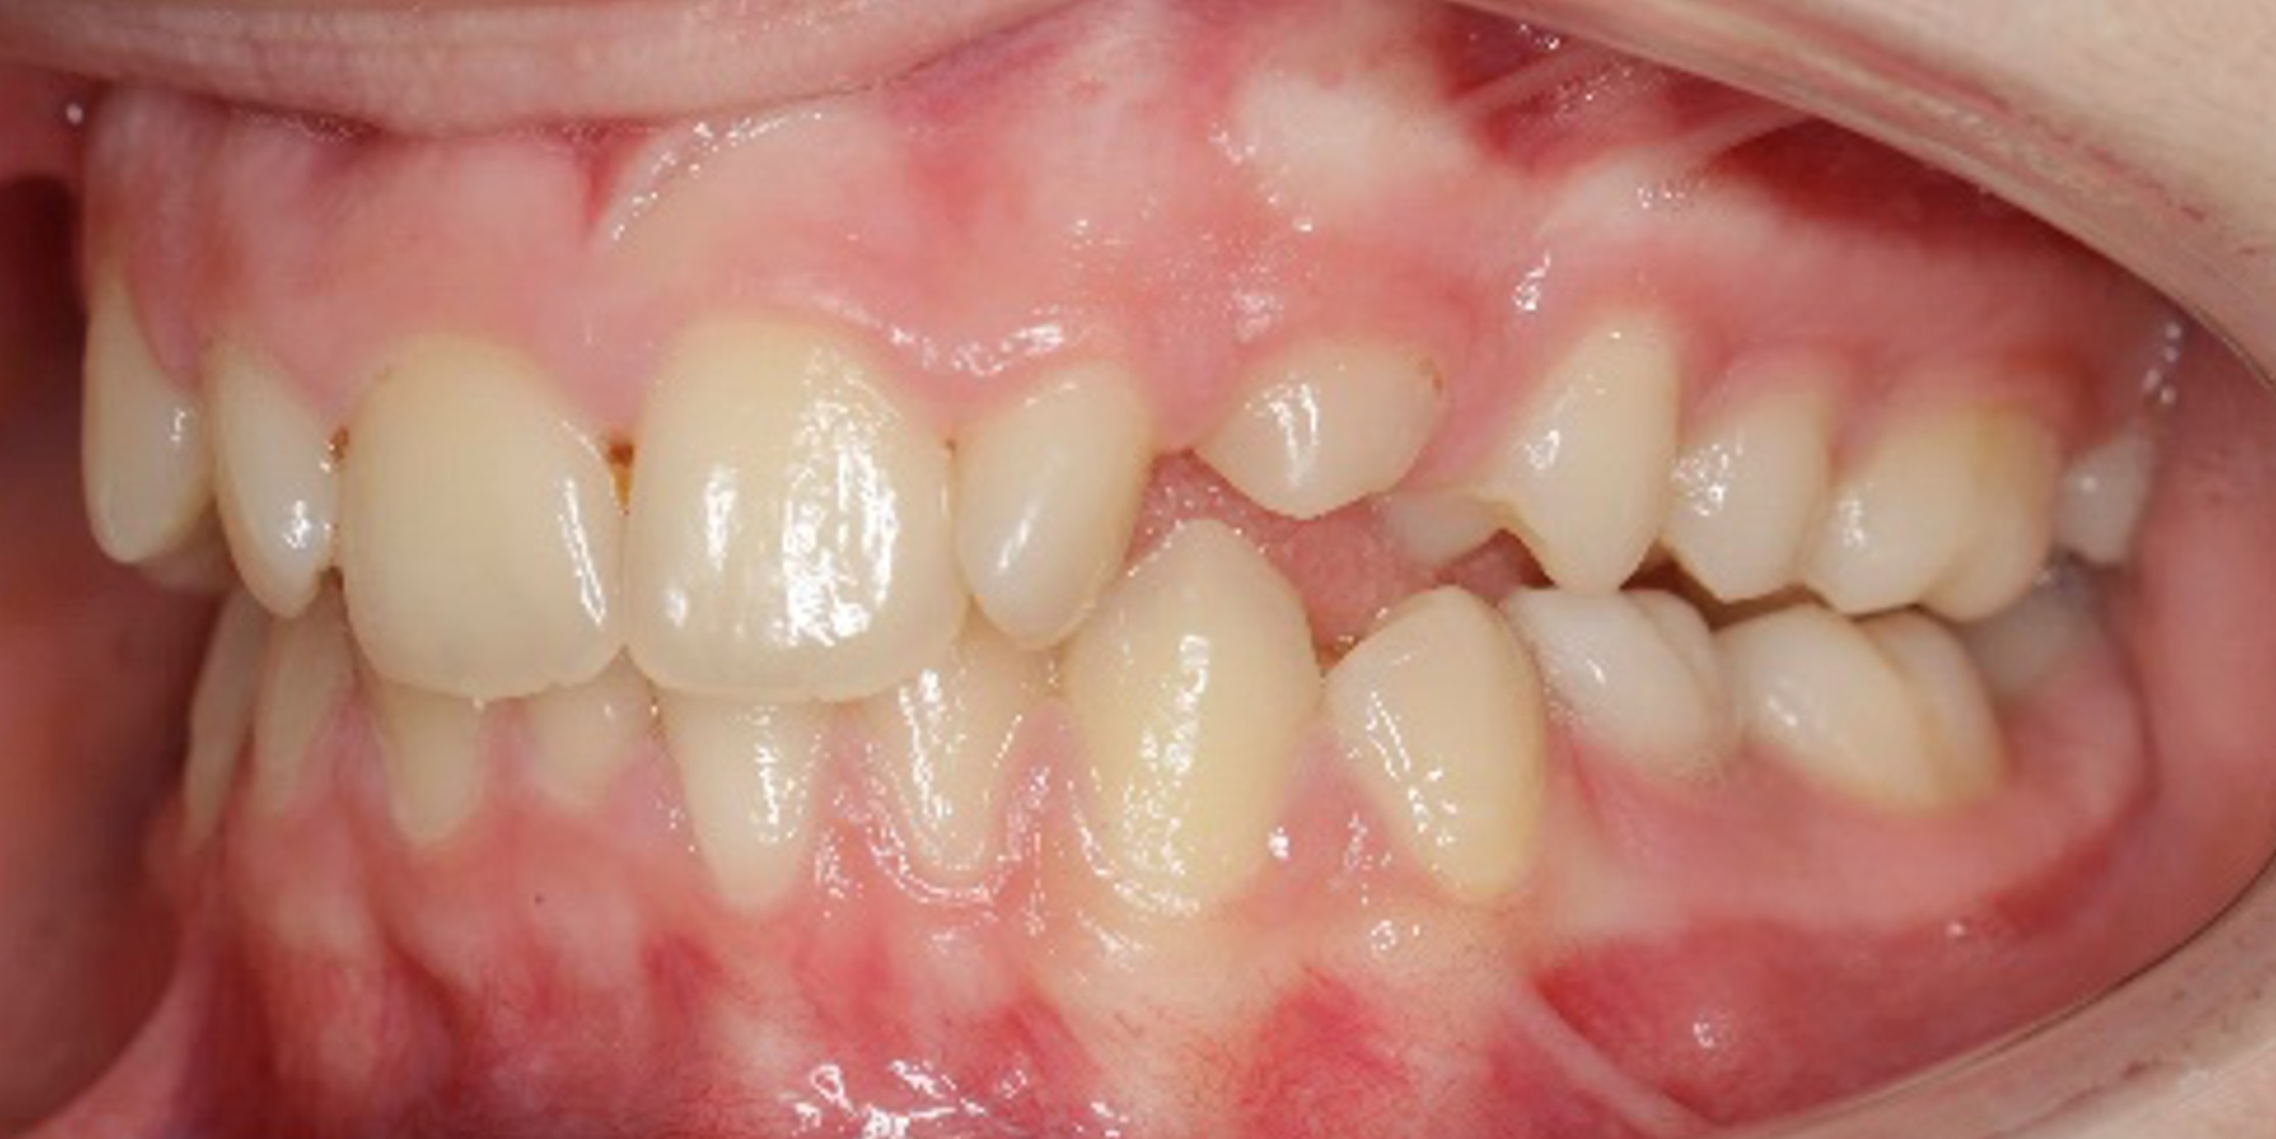

The 14-year-old female patient visited the orthodontic practice in February 2021. The chief complaint was that her upper arch was affecting her confidence in her smile. Upon examination, the patient was found to have a normodivergent facial pattern and a skeletal class II with mandibular retrusion. An intraoral examination revealed narrow arches, a class II molar and canine relationship, deep bite, retroclined upper and lower incisors, and retained teeth 63, 74, and 84.

After undergoing maxillary expansion, Dr. Sorina Blaj assessed the patient again in September 2021, and at that point, tooth 84 had exfoliated, tooth 44 had erupted, and tooth 23 had started to erupt.